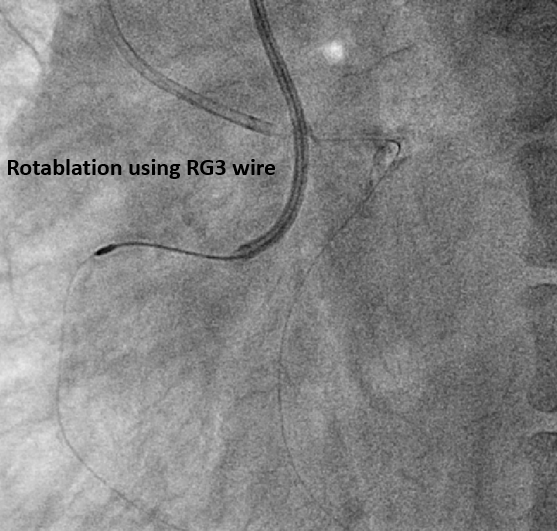

The pLAD ISR was treated first with balloon dilatation followed by DES implantation. An antegrade wire escalation strategy up to Conquest Pro 8-20 for RCA CTO was attempted without success. The wire was left in the subintimal space while a retrograde Sion wire supported by a Finecross microcatheter was advanced through a septal channel to reach the distal CTO cap. The retrograde wire was then exchanged for Gaia 2 and XTA for distal CTO cap penetration. However, a kissing wire technique could not be achieved within the CTO body. Following multiple unsuccessful attempts, the Carlino technique was performed via both the antegrade and retrograde microcatheter. Although a retrograde Fielder FC wire could cross the lesion to the antegrade guiding catheter, this could not be followed by a microcatheter. The retrograde Fielder FC wire was then advanced into the antegrade Tornus microcatheter which also couldn¡¯t cross the lession. Consequently, the retrograde wire was exchanged to RG3. Successful tip-in and externalization with RG3 was achieved afterwards. An antegrade 1.0mm balloon failed to traverse the heavily calcified CTO segment. Therefore, antegrade rotational atherectomy was performed using a 1.25mm burr over the RG3 wire. Following that, the Tornus microcatheter was able to cross the lesion into the distal RCA. A Sion wire was advanced to the distal RCA and the RG3 wire was retrieved. Subsequent balloon dilatation and implantation of two DES were successfully completed

Bi-directional Carlino technique could facilitate intraplaque wire tracking. Usually, after externalisation by RG3 wire, an antegrade microcatheter is advanced distal to the CTO segment for wire exchange, such as a Rotawire in preparation for rotablation. However, in this case, the severe calcification prevented antegrade microcatheter passage. Although the RG3 wire is known to be compatible with rotational atherectomy due to its smaller diameter, its clinical use in this situation is rare. Our case demonstrates the feasibility of performing rotablation over an RG3 wire when neither antegrade nor retroagrde microcatheter passage across the CTO segment is possible.